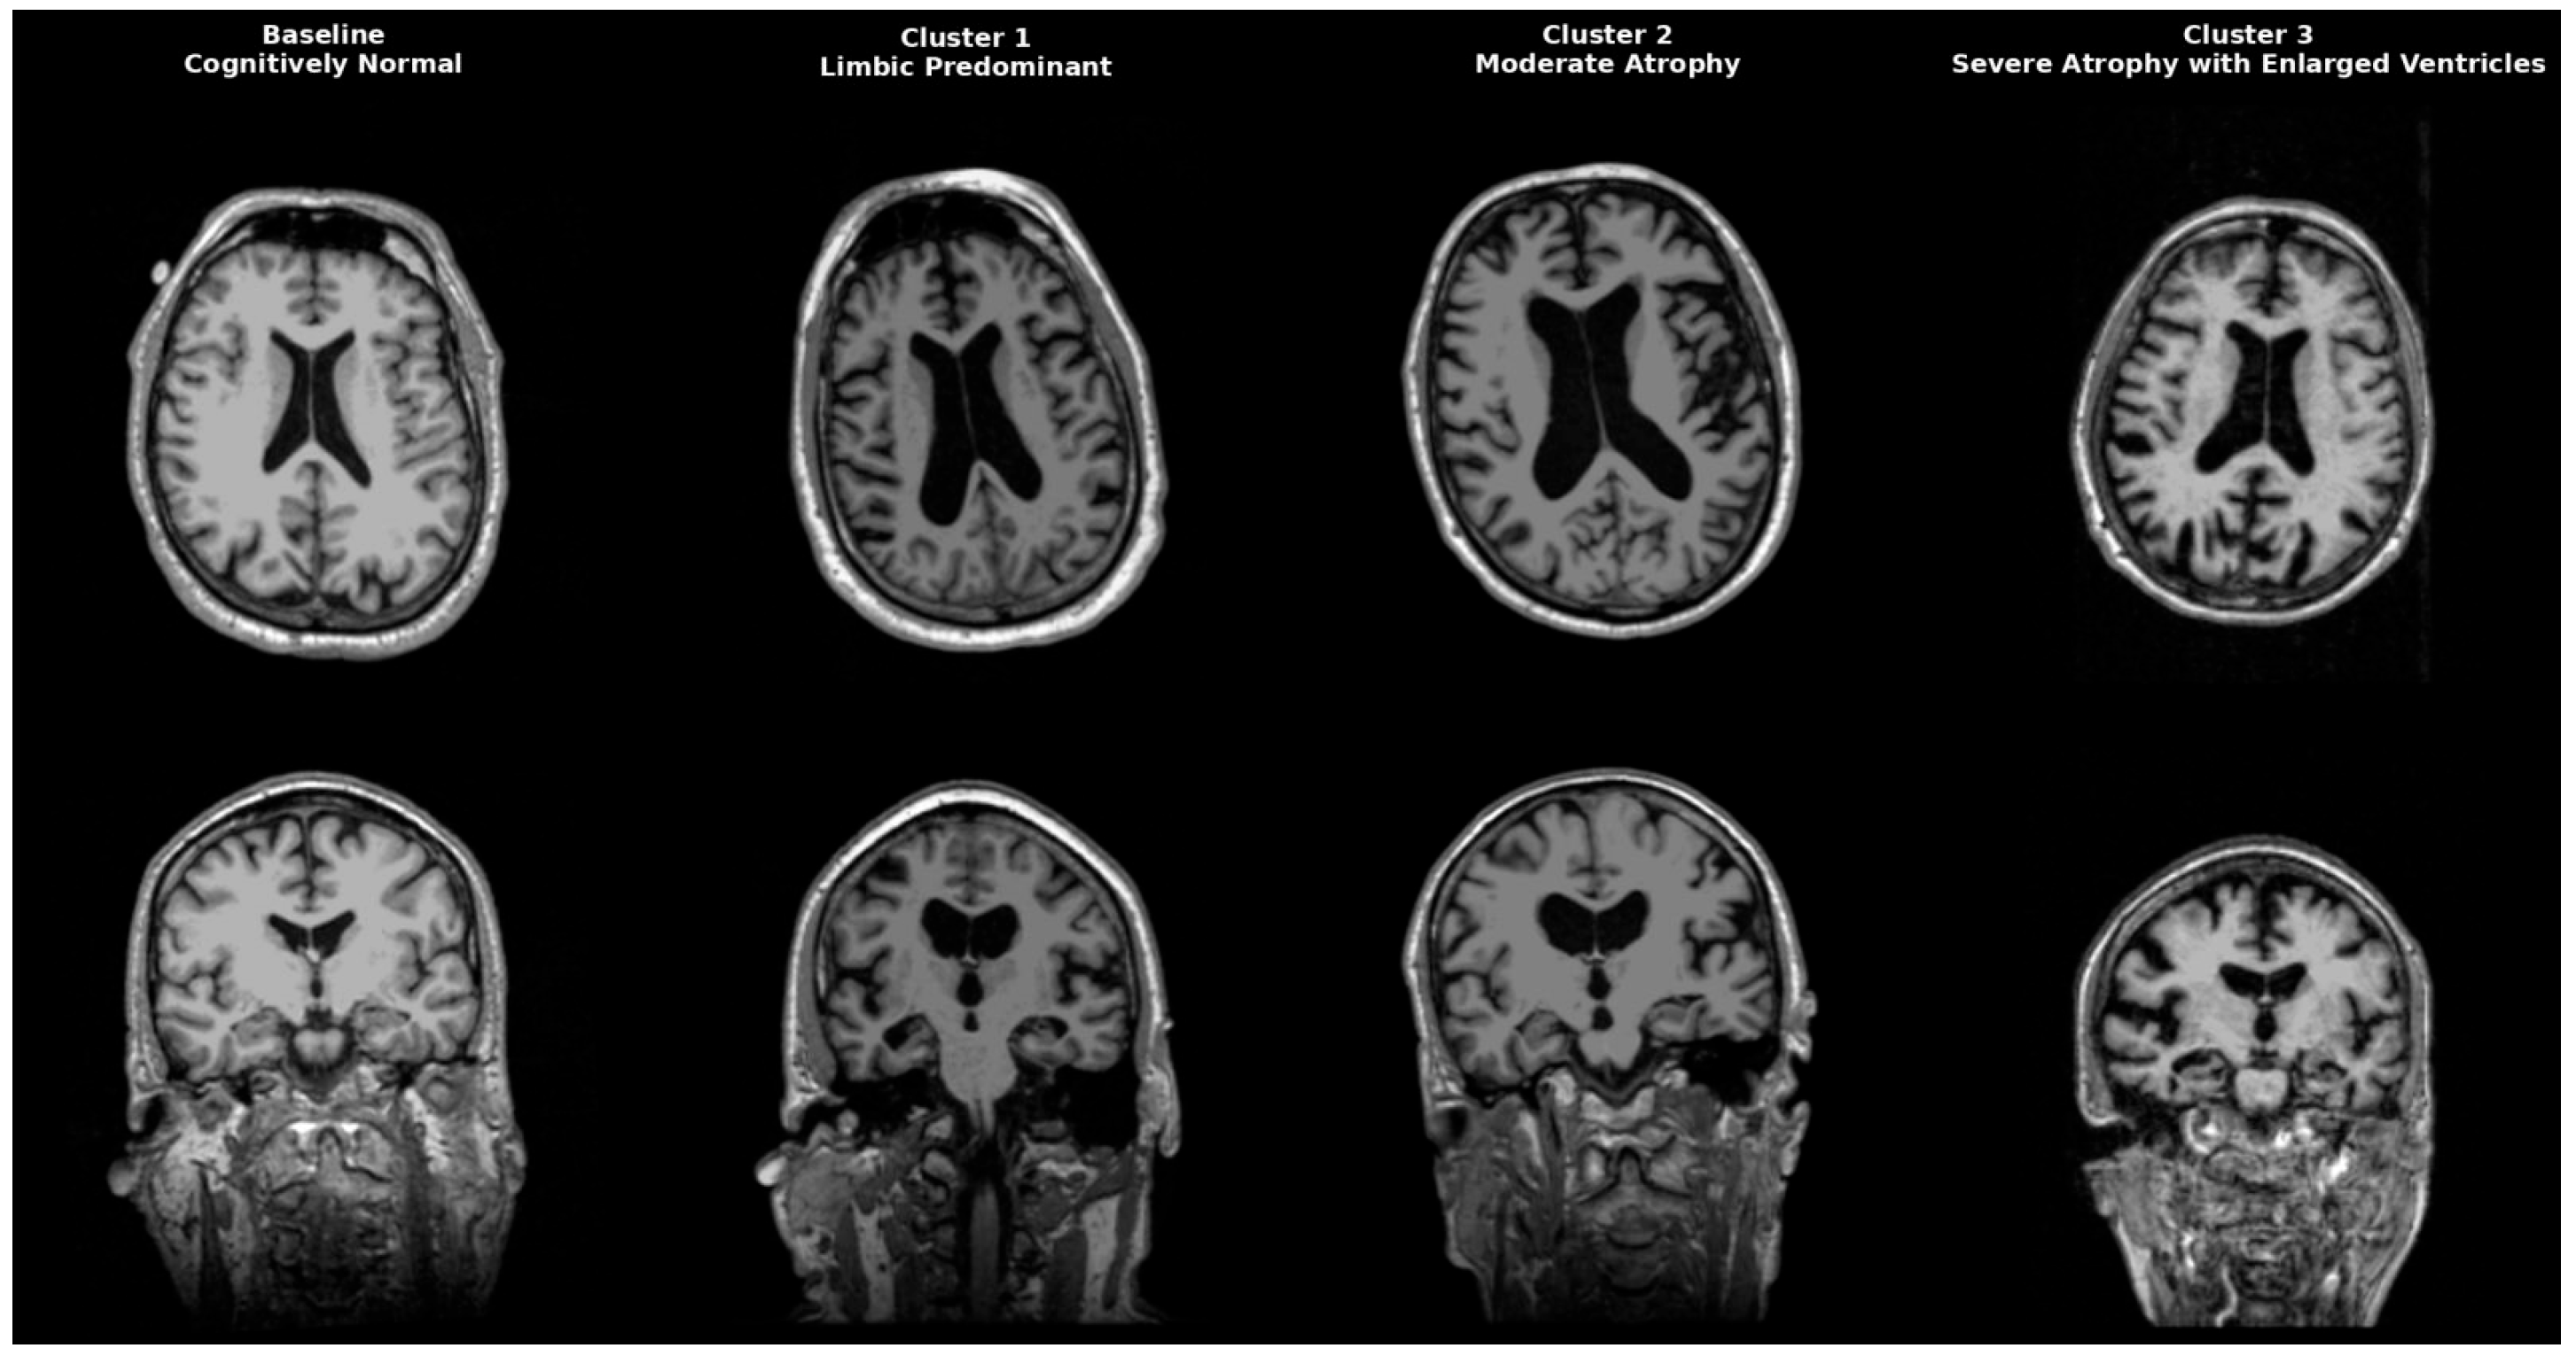

AD is a heterogeneous neurodegenerative disorder that could be classified anatomically and biologically into distinct groups. Neuropathological studies post mortem first identified limbic predominant, hippocampal-sparing, and typical AD. Interestingly, patients with the hippocampal-sparing type died earlier and were men, while those with the limbic-predominant type were women who died older [17]. Neuropathological subgroups were later replicated in imaging cohort studies, solidifying AD variety in atrophy patterns. Representative MRI scans of each identified cluster are shown in Figure 4, highlighting the limbic-predominant (Cluster 1), volume-preserved (Cluster 2), and diffuse atrophy with ventriculomegaly (Cluster 3) subtypes, alongside a cognitively normal baseline for comparison. While our clustering primarily focused on structural and CSF-derived biomarkers, future research might include epigenetic and transcriptomic signatures to improve endophenotype definitions. Recent studies indicate that DNA methylation, microRNA regulation, and gene expression networks impact amyloid processing, tau phosphorylation, and neuroinflammation, influencing regional vulnerability in AD [18,19,20]. These molecular aspects could increase biological accuracy and help link imaging-based subtypes with their cellular mechanistic profiles.

Figure 4.

Representative MRI scans of Alzheimer’s disease subtypes identified by clustering. Axial (top row) and coronal (bottom row) T1-weighted MRI images illustrate a cognitively normal baseline (leftmost column) compared to three distinct AD clusters. Cluster 1 (Limbic-predominant) shows marked hippocampal and amygdala atrophy with relative cortical preservation. Cluster 2 (Volume-preserved, moderate atrophy) demonstrates largely preserved cortical and subcortical volumes despite abnormal CSF biomarkers. Cluster 3 (Diffuse atrophy with ventriculomegaly) exhibits widespread cortical thinning and enlarged ventricles (hydrocephalus ex vacuo), consistent with advanced disease.